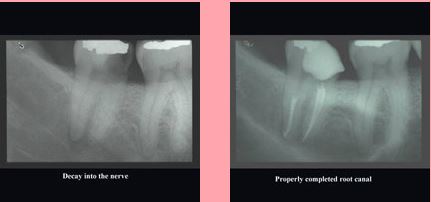

The photograph on the left shows decay into the nerve.

The photograph on the right shows a properly completed root canal.